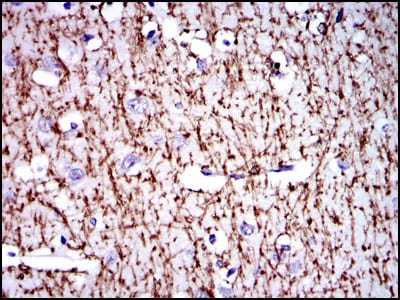

- Immunohistochemical analysis of paraffin-embedded human brain tissues using MBP mouse mAb with DAB staining.